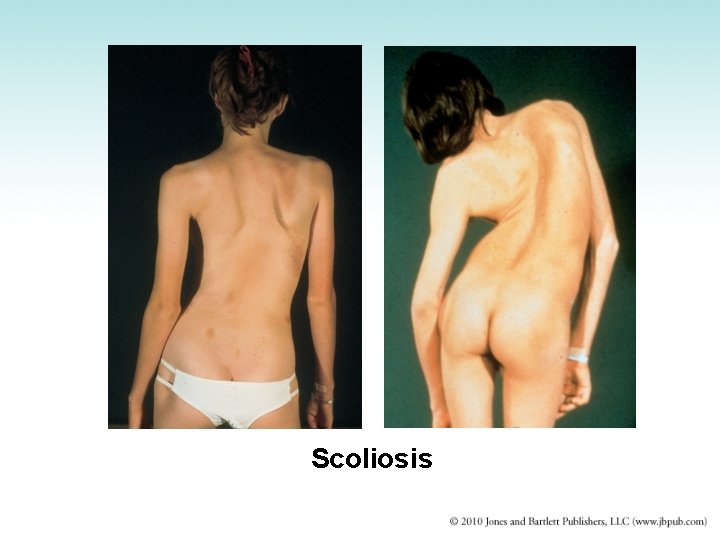

Scoliosis • • Abnormal lateral curvature of spine Occurs in 4% of the population Most cases are idiopathic, occurs in adolescence Can lead to asymmetry of trunk and ↓size of thoracic cavity • One shoulder is higher than the other; pelvis is tilted • Large curvatures cause pronounced disabilities • Treatment: depends on extent of curvature

Scoliosis